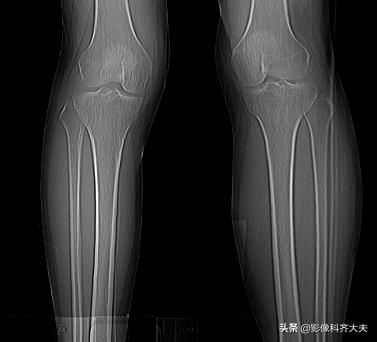

例:右胫骨骨挫伤

右胫骨骨挫伤-平片正常

右胫骨骨挫伤-CT正常

右胫骨骨挫伤-MRI清晰显示病灶位置

胫腓骨骨挫伤

胫腓骨对应性骨挫伤